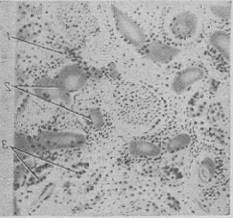

Зміни нирок при М. б. носять вторинний характер. Патогенетично мієломна нефропатія («мієломна нирка») пов'язана в першу чергу з проходженням через нирковий фільтр патологічних білкових тіл, що утворюються в результаті специфічної секреторної активності мієломних клітин. Таким чином, мієломна нефропатія являє собою справжній «нефроз виділення». Клінічно вона характеризується протеїнурією (див.) при відсутності гематурії, набряків, гіпертонії і ретинопатії. В подальшому розгортається картина ниркової недостатності: олігурія з низькою питомою вагою сечі і прогресуюча азотемія з явищами уремії, аж до розвитку фібринозного перикардиту і коми, завершується летальним результатом. Причиною розвитку уремії (див.) при мієломної хвороби є не стільки зміни клубочкового апарату, скільки порушення сечовиділення по канальцям, буквально забитих білковими масами (рис. 10). Відому роль у зниженні ниркової фільтрації при М. б. можуть грати і внепочечные фактори: артеріальна гіпотонія і гиперонкия плазми (внаслідок гиперпротеинемии). Ці фактори при наявності обтурації канальців нирки патологічними білками можуть призвести до різкої олігурії, аж до повної анурії.

![]() Рис. 10. Парапротеинемічний нефроз при мієломної хвороби: склероз і круглоклеточная інфільтрація (1) интерстиция нирки; просвіти канальців розтягнуті, заповнені білковими масами (2), епітелій атрофичен; 3 - регенерація епітелію звивистих канальців. |